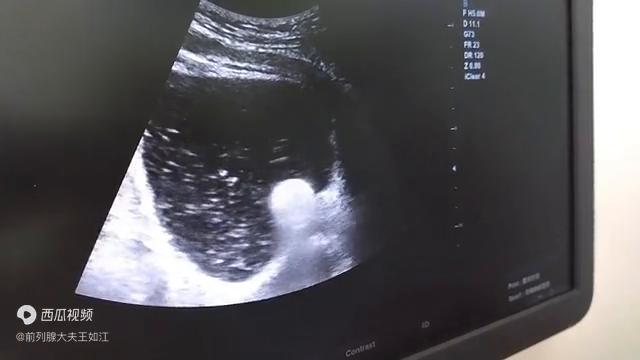

这个时候我们的疏通就利用尿管稍微加一点水囊往里面一捅,我们就可以看出有大量的絮状物、片状物,这都是脱落的钙化灶组织。从尿道里面吐出来进入到膀胱肉眼是清晰可见的。这就是我们利用尿管做的尿道疏通,就和清理下水道。

刚才这个图大家看都很清楚,大量的白色絮状物,斑片状的物质,而且清晰地看到了尿道内口被水囊扩开的一个过程。这个尿道扩张疏通术,它只是用的最简单的一些普通导尿管,巧妙的用了它水囊的这种柔软的,无创的扩张作用。起到了这个效果。